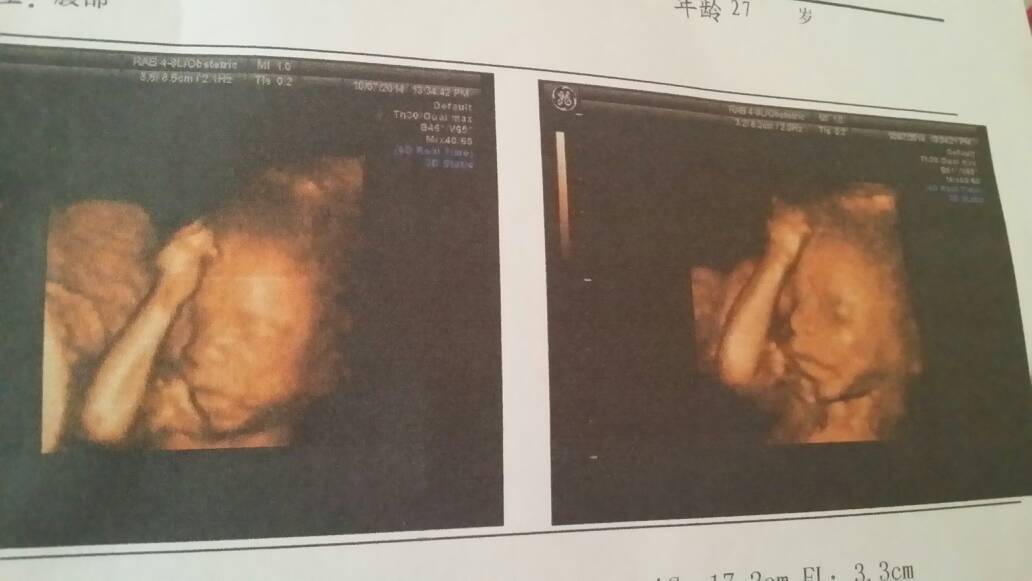

四维归来,本来是想要女孩的,检查是男孩有点小失望,不过看着他的照片还是蛮开心的

这个时候通过B超基本都是可以比较准确的鉴定出胎儿的性别的,男孩女孩都是比较好的。